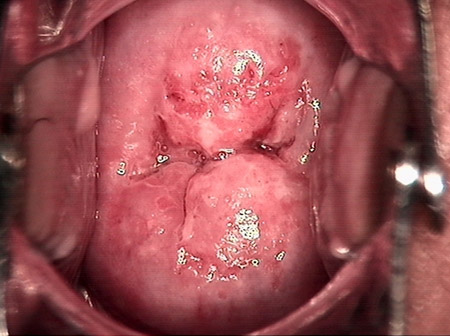

婦科leep手術 宮頸息肉

• 宮頸息肉宮頸息肉